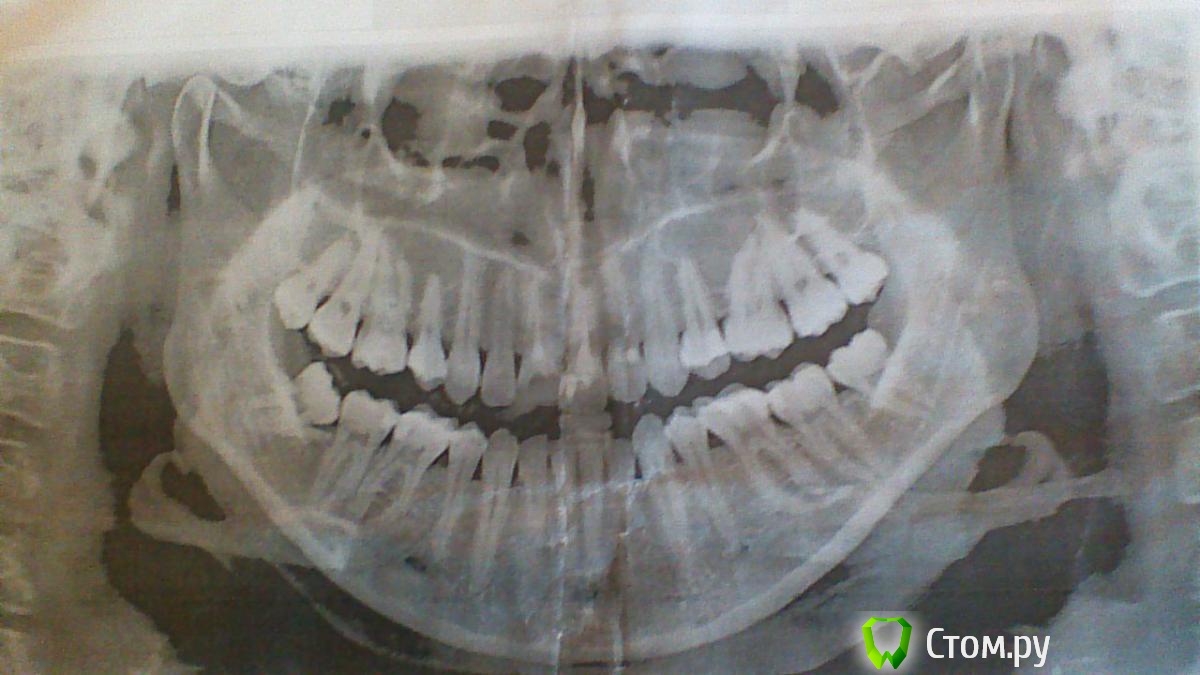

Состояние до лечения на снимках:

снимок 2 - панорамный.

Снимки показали наличие гранулемы на 11 зубе.